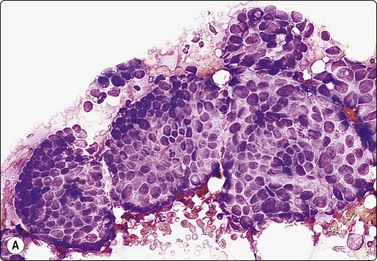

image image image

Fig. 7.8 Lactating breast

Dispersed acinar cells with abundant pale and fragile cytoplasm, rounded nuclei and prominent central nucleoli; background of lipid secretions (A, MGG, HP; B, H & E, HP oil); (C) Corresponding tissue section (H&E, IP).

Criteria for diagnosis

Cellular smears,

Poorly cohesive, mainly dispersed epithelial cells of acinar type,

Cells have abundant fragile cytoplasm with secretory vacuoles and frayed borders,

Rounded vesicular nuclei and central nucleoli,

Dirty background due to lipid secretion and stripped nuclei with prominent nucleoli,

Single bipolar nuclei difficult to find.

FNB is very useful in reducing surgical intervention to a minimum during pregnancy and lactation. The pattern seen in FNB smears of ‘lumps’ in a pregnant or lactating breast can be problematic to inexperienced eyes and cause concern for malignancy.93,94 Smears are usually cellular. The cells are enlarged and arranged in loose groups or singly. The cells have an abundant fragile cytoplasm, vacuolated and finely granular. Nuclei are round, central, larger than the usual ductular cells, and have distinct small nucleoli (Fig. 7.8B). Some epithelial nuclei are stripped of cytoplasm. Single naked bipolar/oval nuclei are difficult to find. The background of abundant milky secretion with numerous lipid droplets seen as vacuoles is characteristic of actively secreting breast tissue and is the main clue to the diagnosis (Fig. 7.8A).